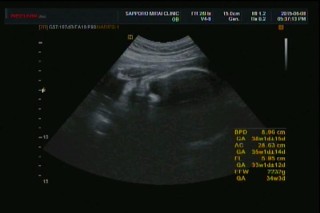

写真:32w2d:anmamaさん:1994g

1994gの女の子です☆ 口半開き、目も半開き、 完全に私の癖を引き継いだようww しかし我が子は可愛いですな^^